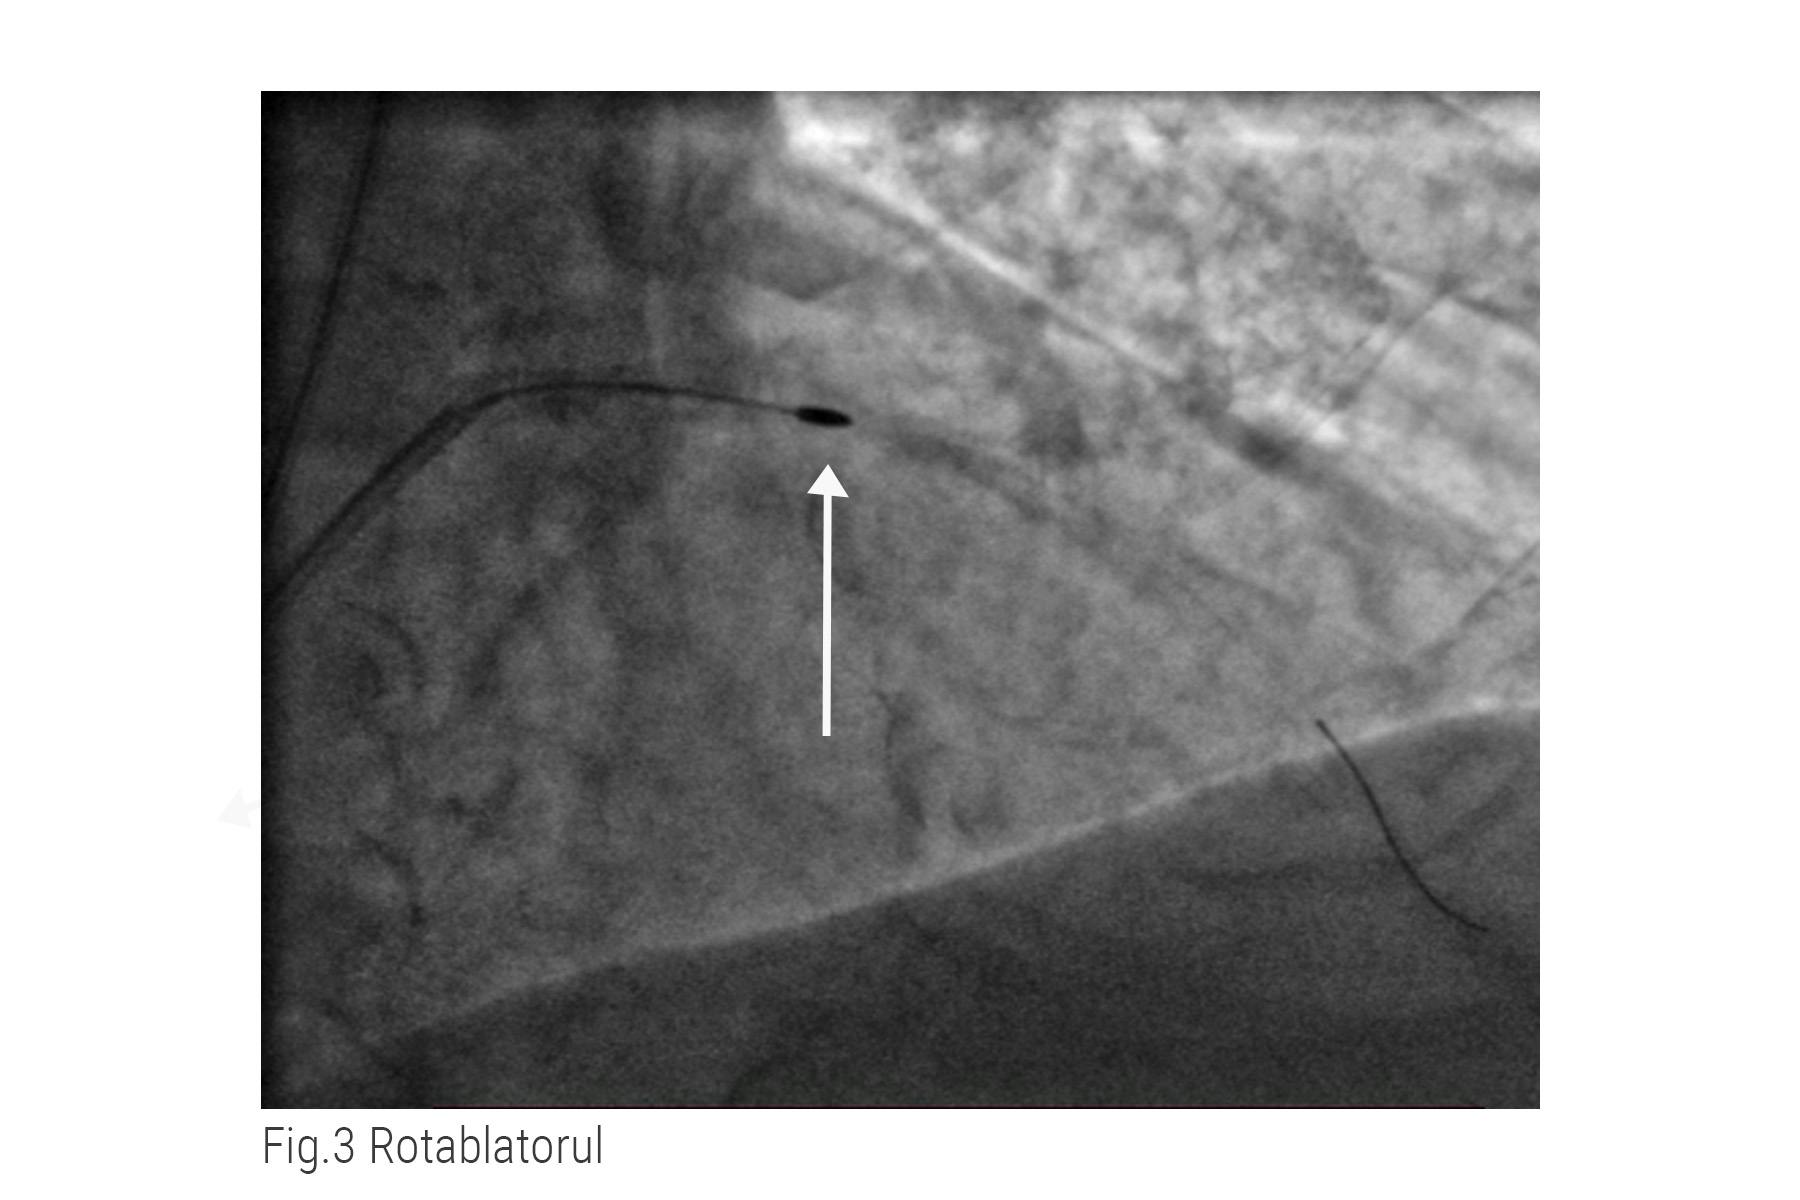

Pentru stenoza severă din artera descendentă anterioară, medicul intervenționist a apelat la procedura de rotablație.

În imagine se poate observa device-ul oval pe care medicul îl înaintează în arteră pentru a dezintegra calciul de pe pereții acesteia. După ce vasul este eliberat, dilată zona cu balon și implantează stentul metalic. (fig. 3)